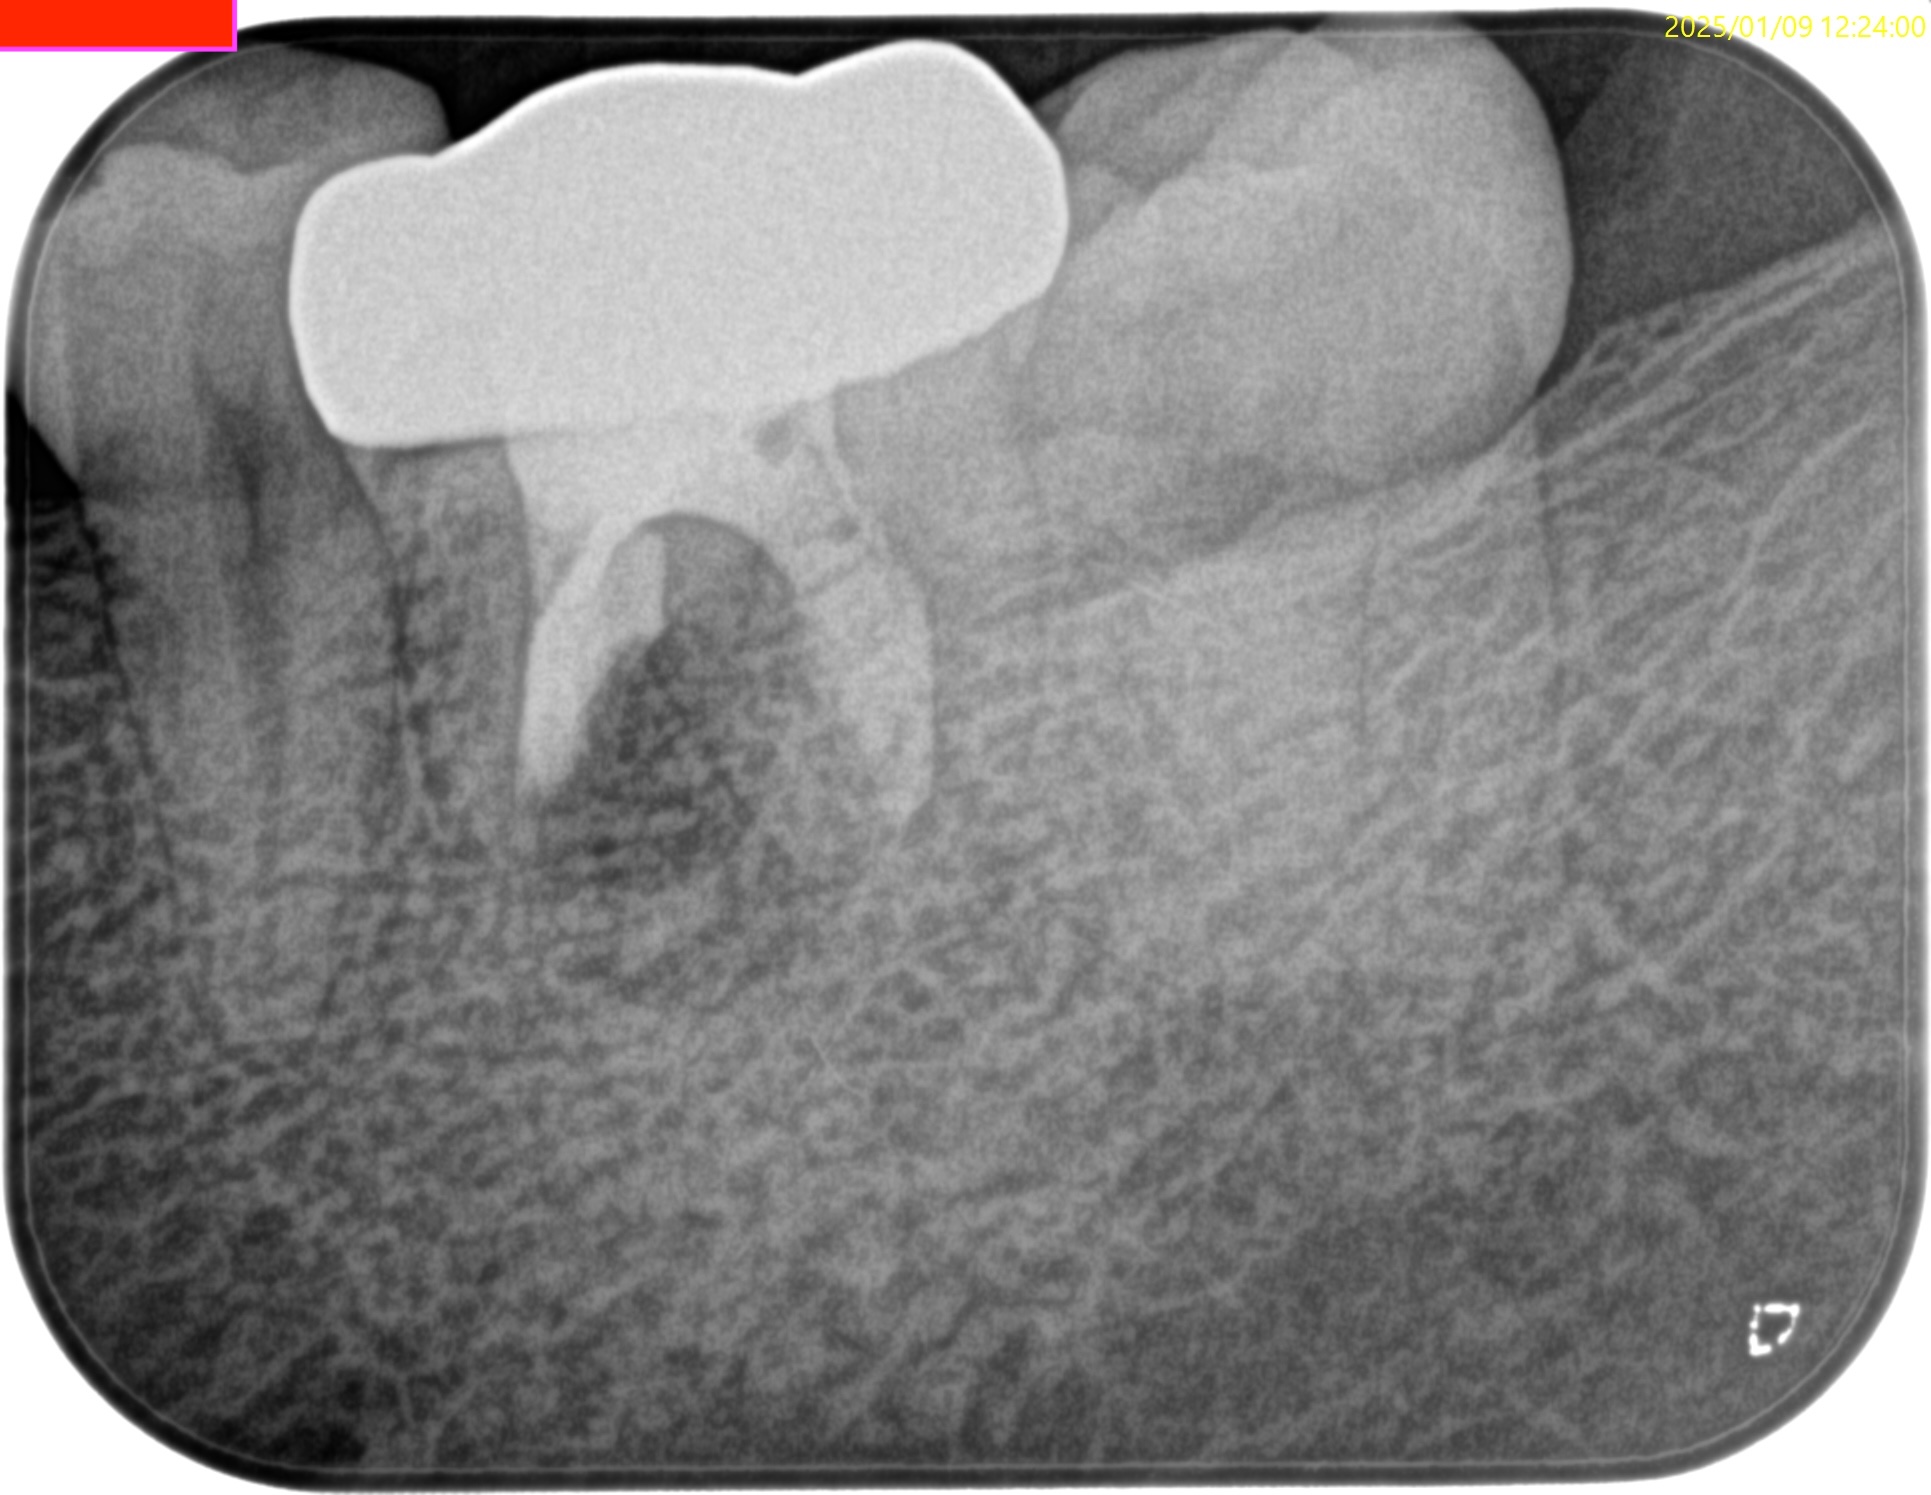

#19 M Apicoectomy(2025.1.9)

術後にPA, CBCTを撮影した。

問題はないだろう。